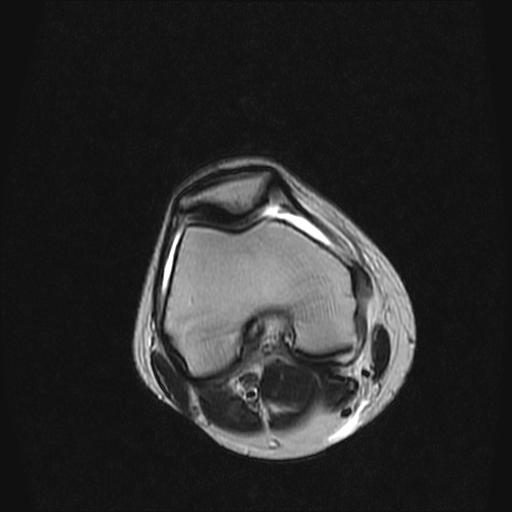

40岁男性,右膝关节外伤,x光平片示,髁间隆突撕脱骨折。

3、关节腔积液。

前交叉韧带撕裂,关节腔积液.

半月板1-2级损伤   前交叉韧带撕裂伤   关节腔少量积液  诸骨未见新鲜外伤性改变

前交叉韧带撕裂,关节腔积液,支持!

半月板1-2级损伤   前交叉韧带撕裂伤   关节腔少量积液

3、滑膜炎伴关节腔积液。

除了关节积液外并无韧带撕裂,acl胫侧附着点有2束,正常情况下脂肪信号。此病例应加做压脂像以便观察是否有骨损伤。